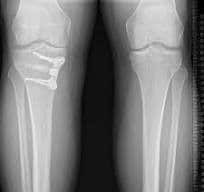

A high tibial osteotomy helps realign the knee joint. In patients suffering from knee arthritis, HTO can delay or avoid partial or total knee replacement by preserving the damaged joint tissue. Surgeons usually perform HTO to treat medial, uni-compartmental osteoarthritis of the knee and/or fix misalignment of bones that form the knee joint.

Pre and post op X-ray HTO